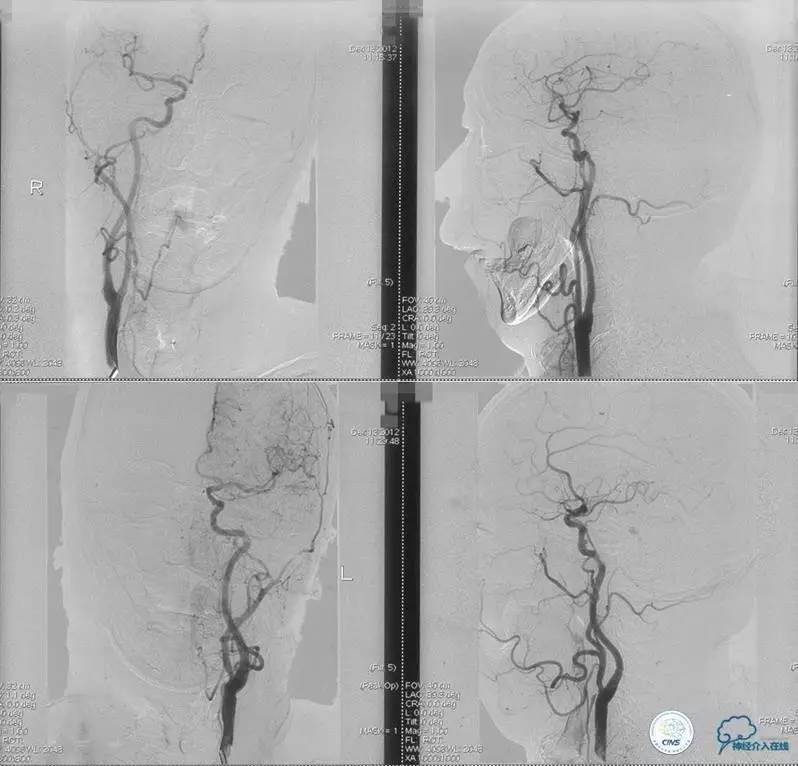

▼入院MR

神经内科保守治疗。

入院第三天,病情转差。

查体:构音障碍加重,右侧肢体肌力降落(近端Ⅱ级,远端0级)。

▼开通

出院情况:头晕症状消失,构音障碍缓解,进食无呛咳,饮水实验(-),右侧肢体远端肌力恢复到Ⅰ级。